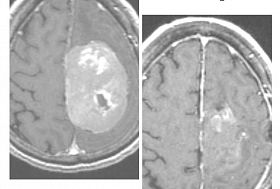

Хирурги из Бурятии спасли пенсионерку с опухолью мозга

Женщина шесть лет отказывалась от операции